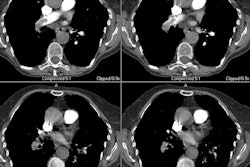

There is evidence of arterial wall thickening (greater than 1.5 mm), stenosis, annuloaortic ecatsi,a or aneurysm formation [1,2,3]. Lesions are long, segmented, and tapered at both ends [2].

PET imaging will demonstrate abnormal tracer uptake in the aortic arch or large thoracic arteries in more than half of affected patients [3].